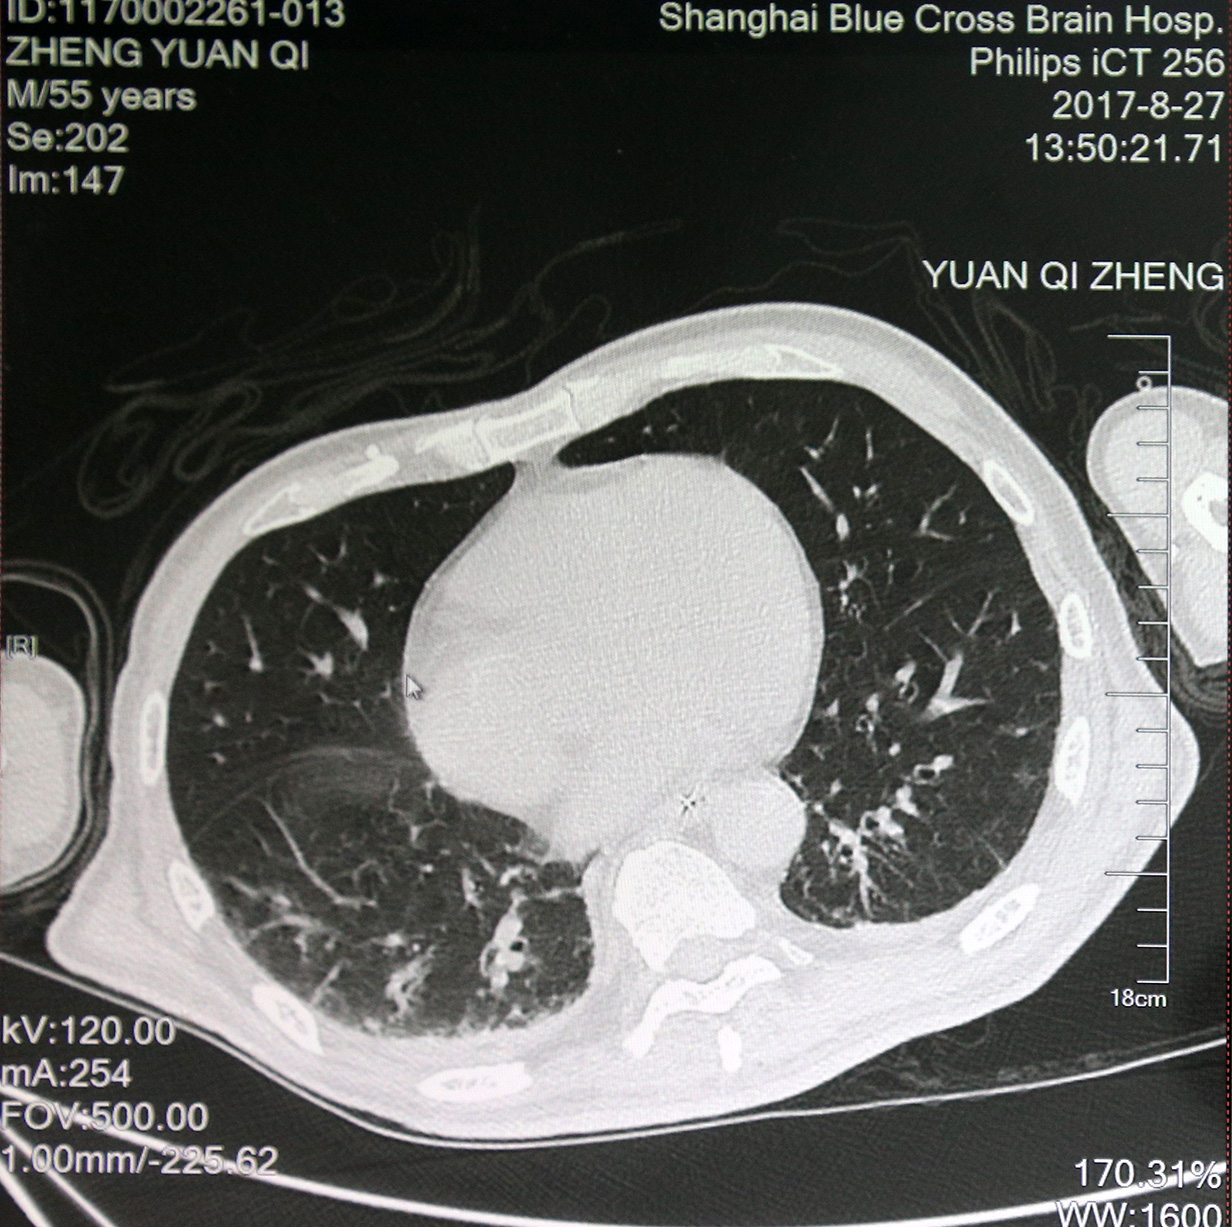

最近肺部CT影像:双肺炎症较前减少

8月8日,郑元齐出现低血压,癫痫大发作,情况十分危急,被紧急送进ICU病房进行抢救后病情平稳。ICU治疗以充分氧合、消除炎症和促醒为主,ICU副主任医师李鲁萍给予纤支镜灌洗治疗控肺吸痰,邀请中医科给予针灸刺激头皮神经末梢促醒,中药活血化瘀等中西医结合治疗,且严密监控病情病症变化。此后,郑元齐反复高热、癫痫、低氧等症状没有再出现,肺部感染得到进一步控制,痛觉越来越敏感,情况一天天好转。

目前,郑元齐从深昏迷状态转为浅昏迷状态,有微小意识,痛觉越来越敏感,对针灸等刺激有弹跳反射,并有明显的情绪反应。眼球可以四周转动视物,一些他亲近的人,熟悉的事物能明显引起他呼吸、心率等生命体征的波动。吞咽和咀嚼功能也恢复良好,经鼻饲管流质饮食转为喂食,可以吃面条、肉类及蔬果等。